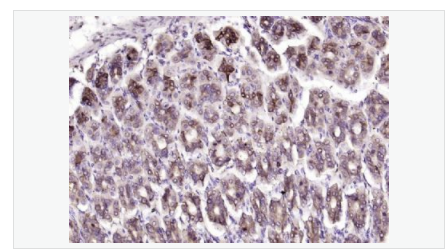

| 產品應用 | ELISA=1:5000-10000 IHC-P=1:100-500 IHC-F=1:100-500 ICC=1:100-500 IF=1:100-500 (石蠟切片需做抗原修復) not yet tested in other applications. optimal dilutions/concentrations should be determined by the end user. |